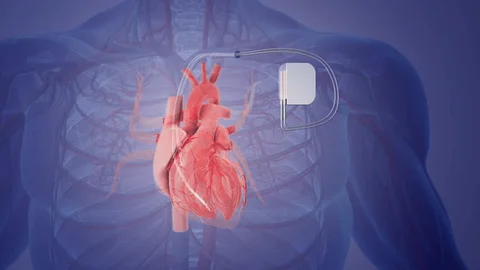

Value added benefits of the Pacemaker Procedure Biventricular:

Value added benefits of the Pacemaker Procedure Double Chamber:

Value added benefits of the Permanent Pacemaker Implantation: